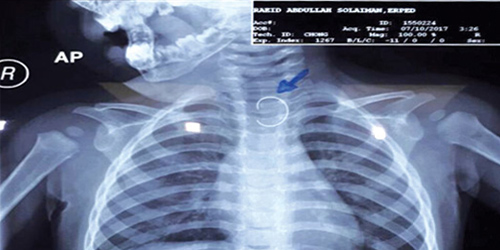

في إطار سلسلة التعامل مع حالات ابتلاع الأجسام الغريبة، نجح فريق طبي بمستشفى الولادة والأطفال بمنطقة نجران من إنقاذ حياة طفل يبلغ من العمر 11 شهراً بعد استخراج سلك معدني ابتلعه، وتسبب في عدم استقرار حالته الصحية. وفي التفاصيل تمت إحالة الطفل من أحد المستشفيات بالمنطقة وبالمعاينة وبعد إجراء الفحوصات الإشعاعية أظهرت النتائج وجود جسم غريب بالمريءء عبارة عن (سلك معدني حاد الطرفين). وبفضل من الله تم استخراج الجسم الغريب بالمنظار بأمان والحالة العامة للطفل مستقرة.